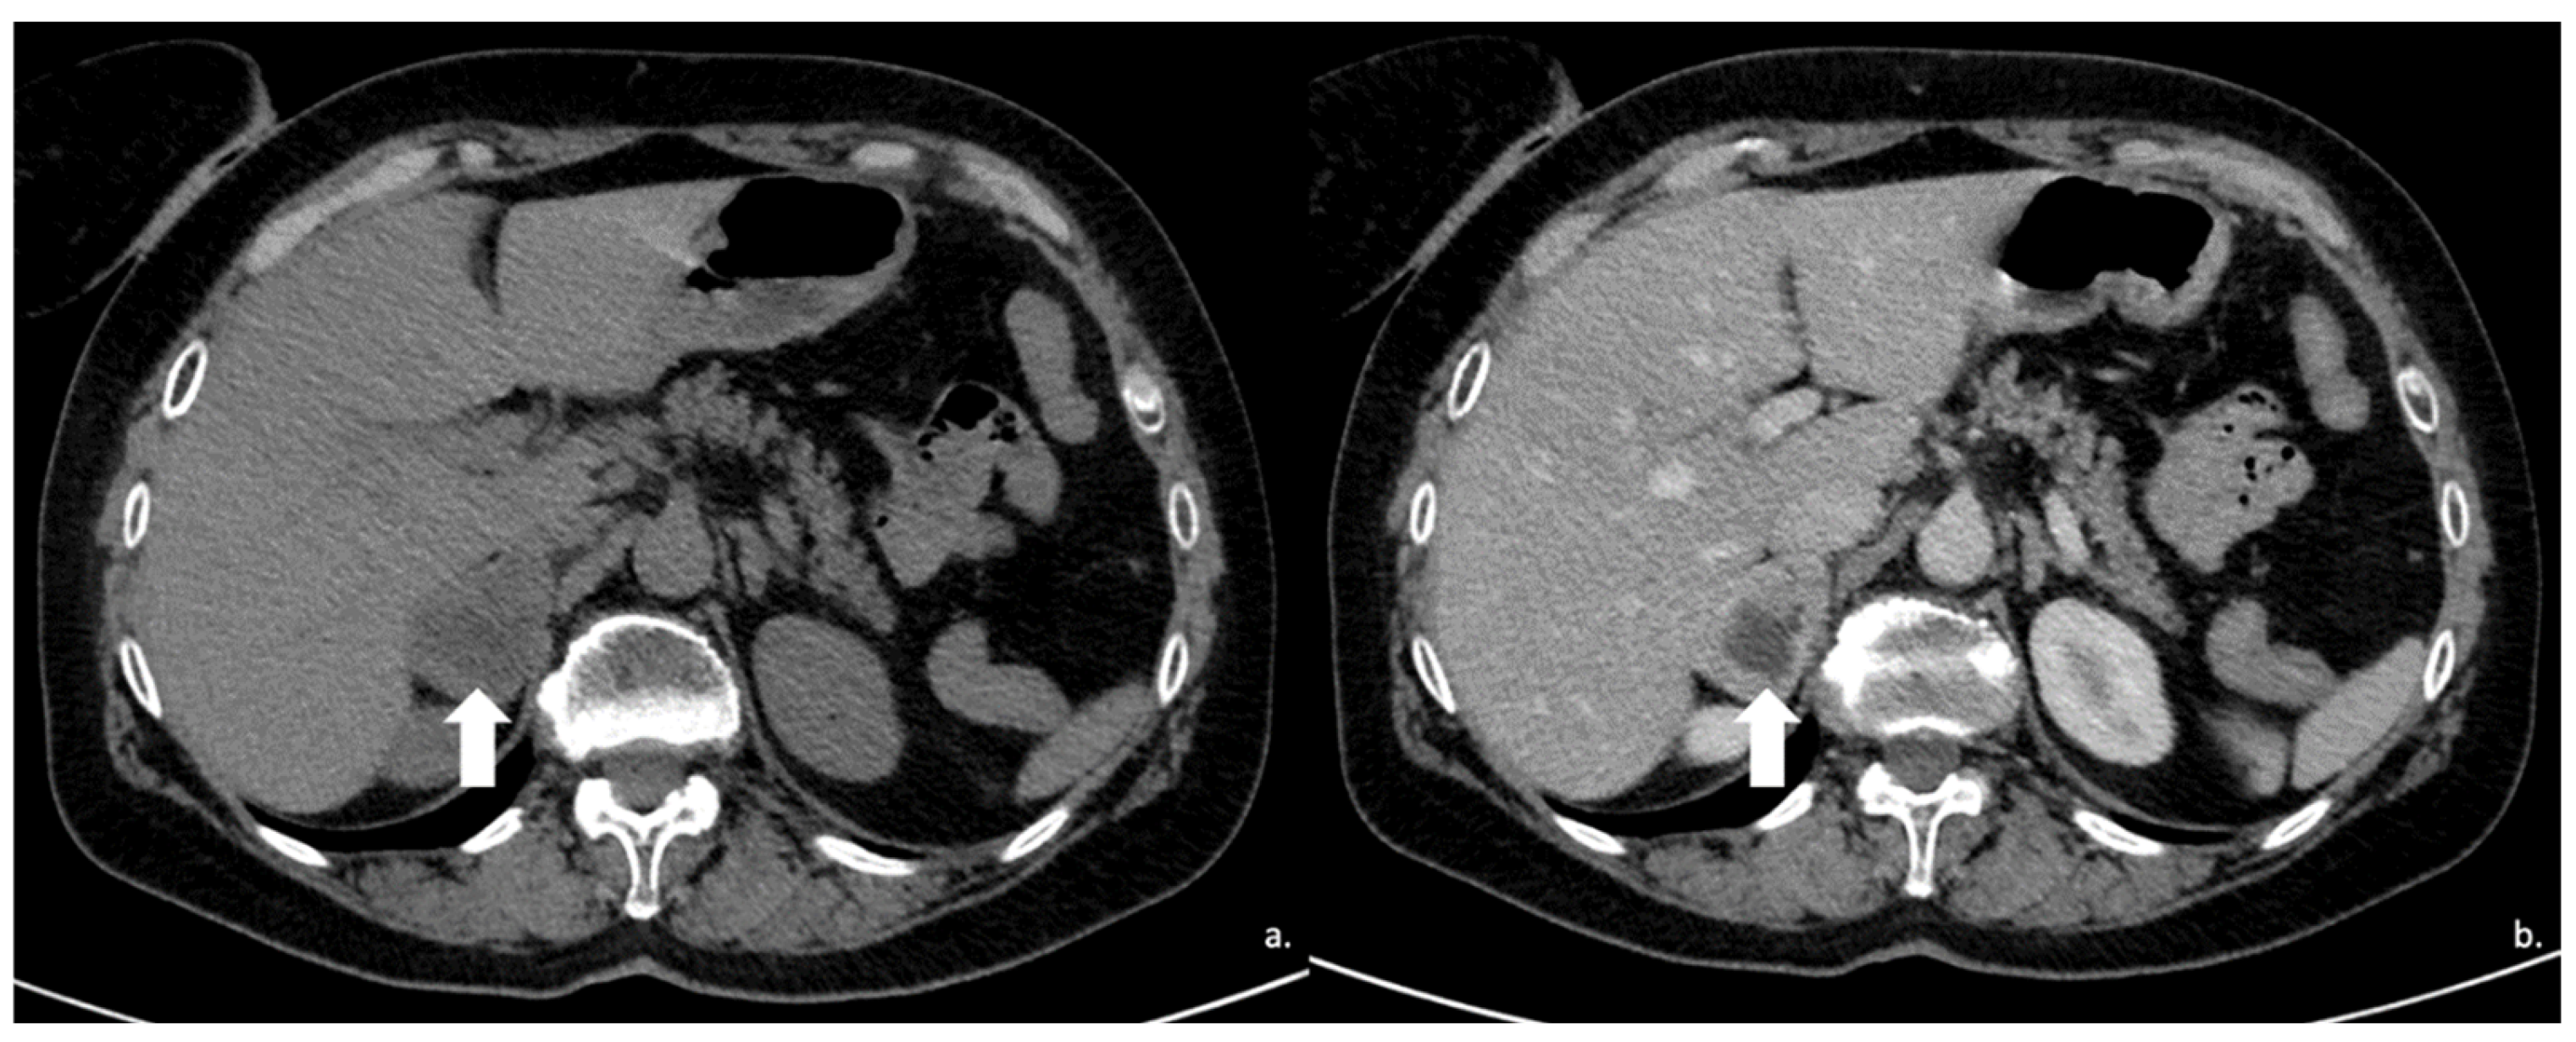

Figure 9.

Voluminous lesion (arrow) of the left adrenal gland measuring 60 × 55 mm with density value > 20 HU on basal CT (A) and inhomogeneous enhancement on venous (B) and late post-contrast phases (C) due to the presence of necrotic and cystic areas. Histological diagnosis of Adrenocortical carcinoma.